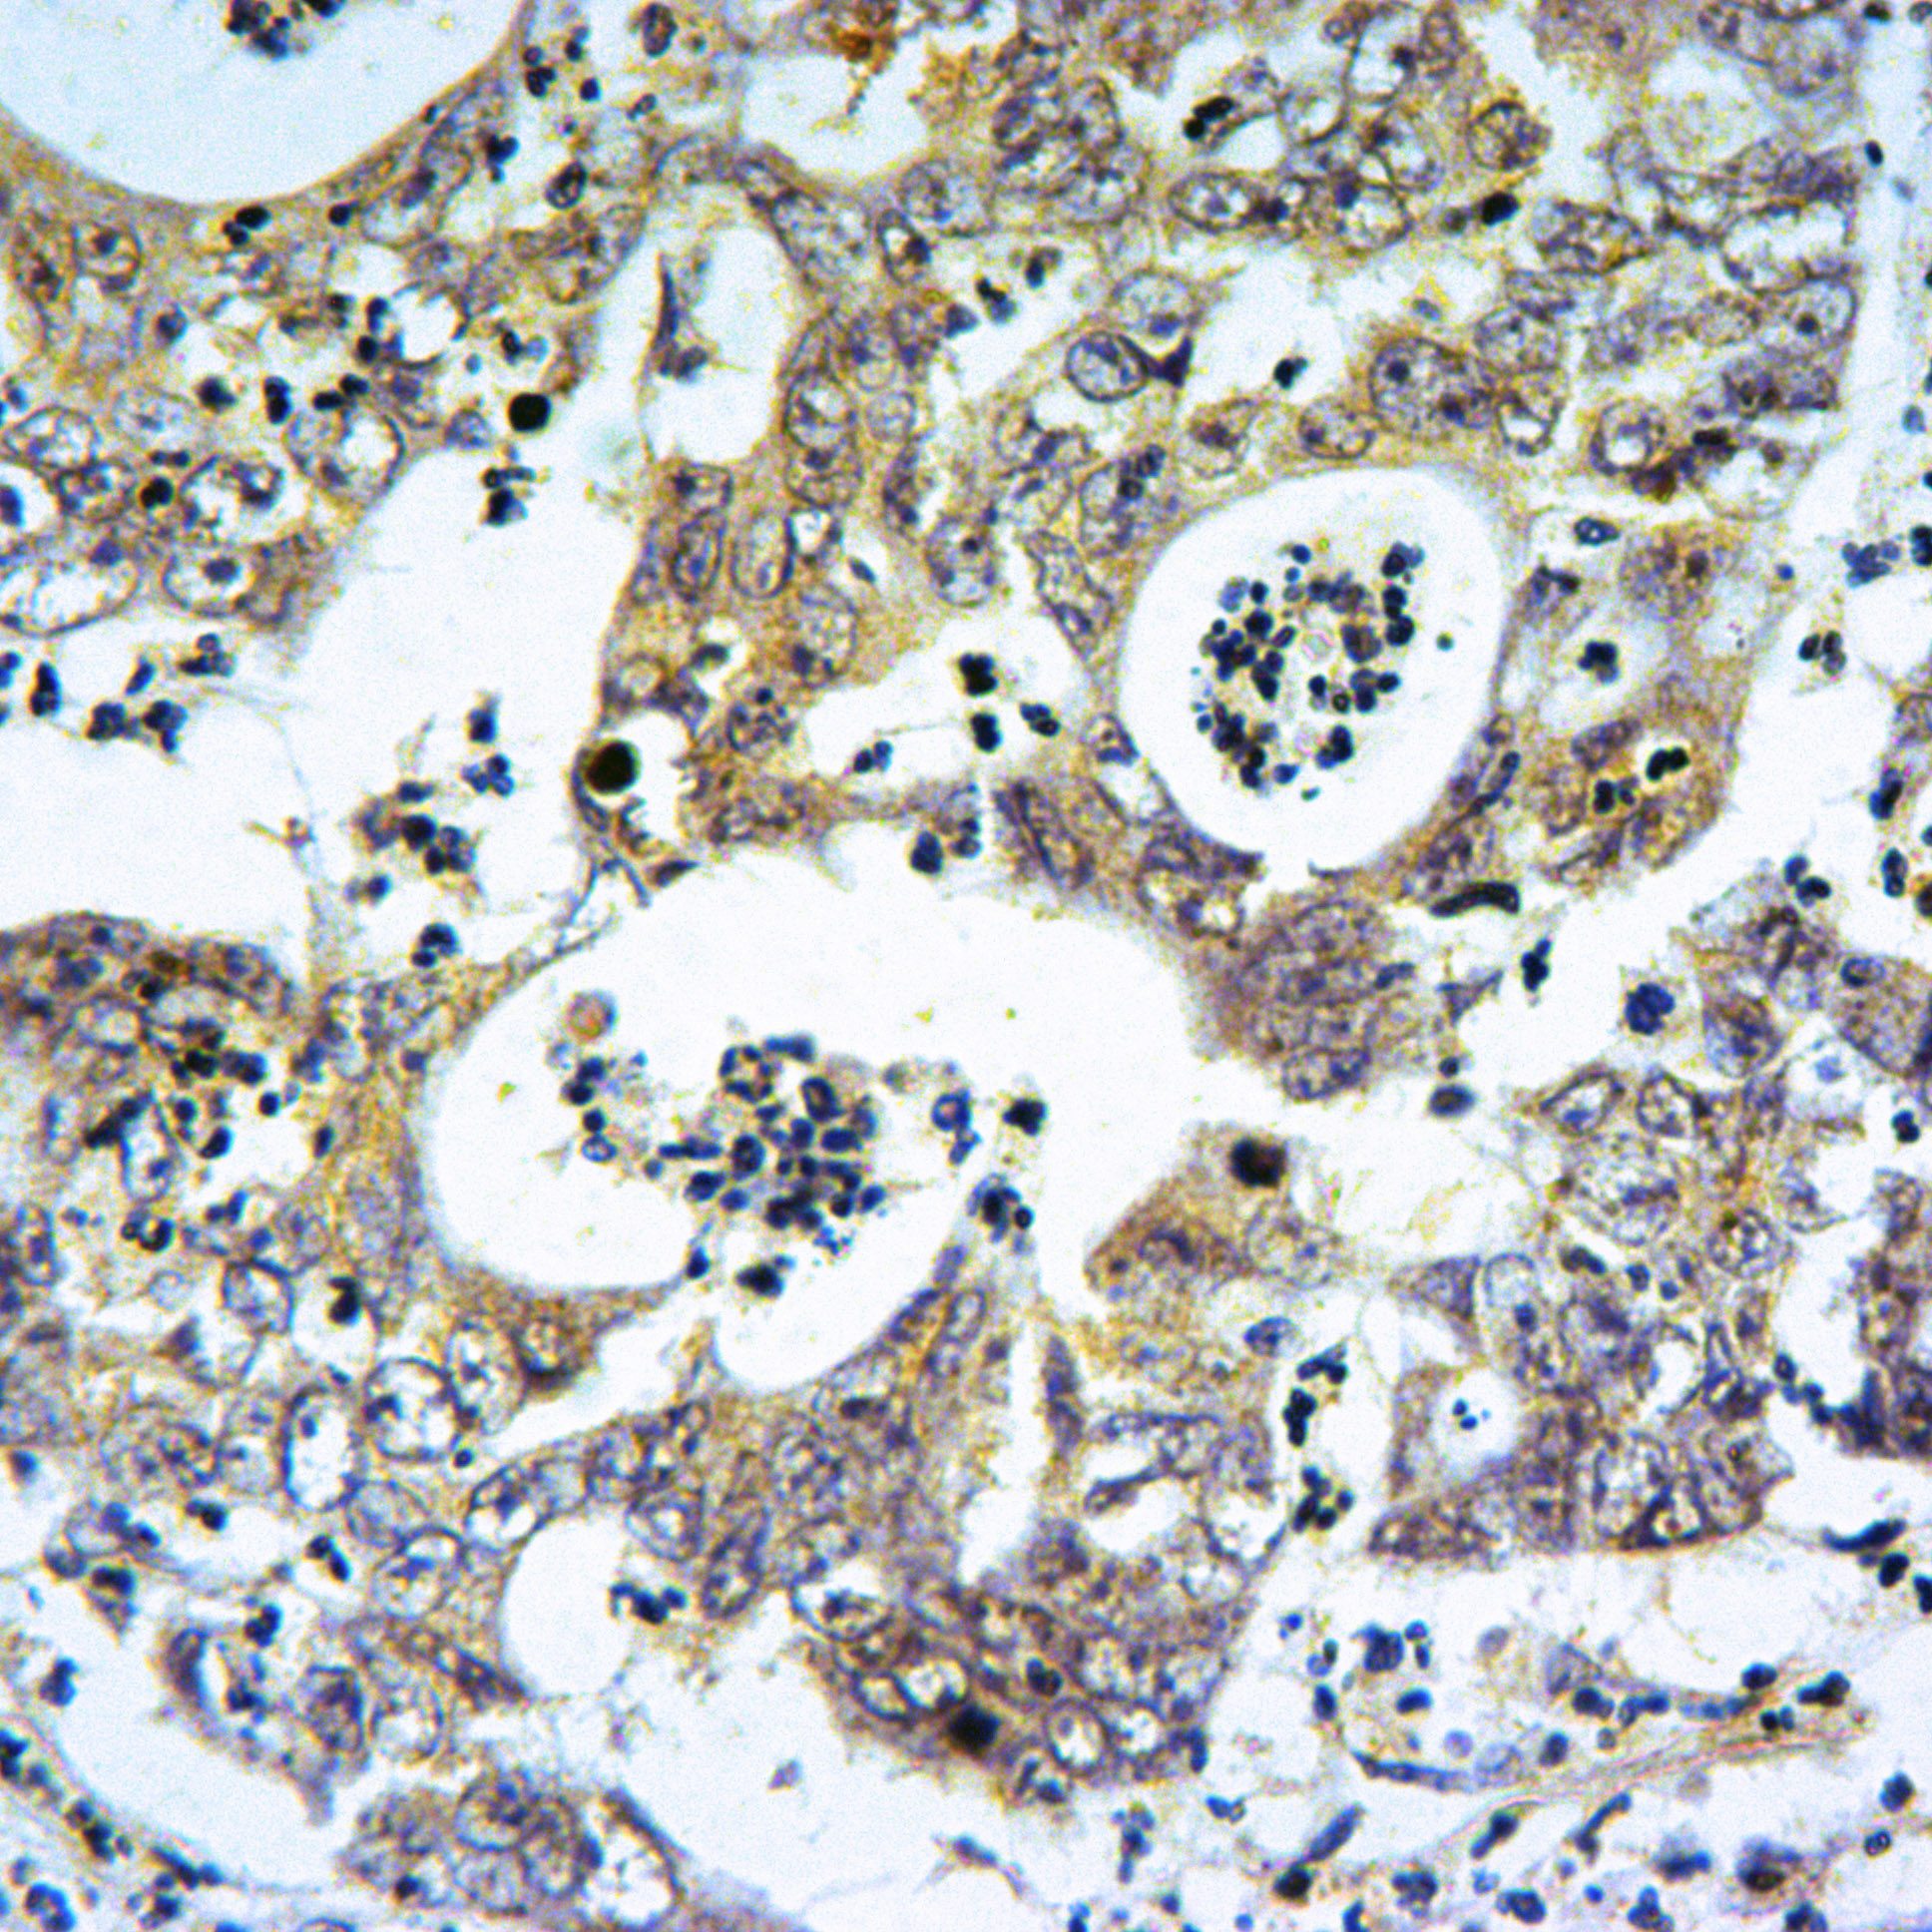

- Immunohistochemistry of paraffin~embedded Human Colorectal cancer using mT0R (Ser2481) antibody at dilution of 1:50.